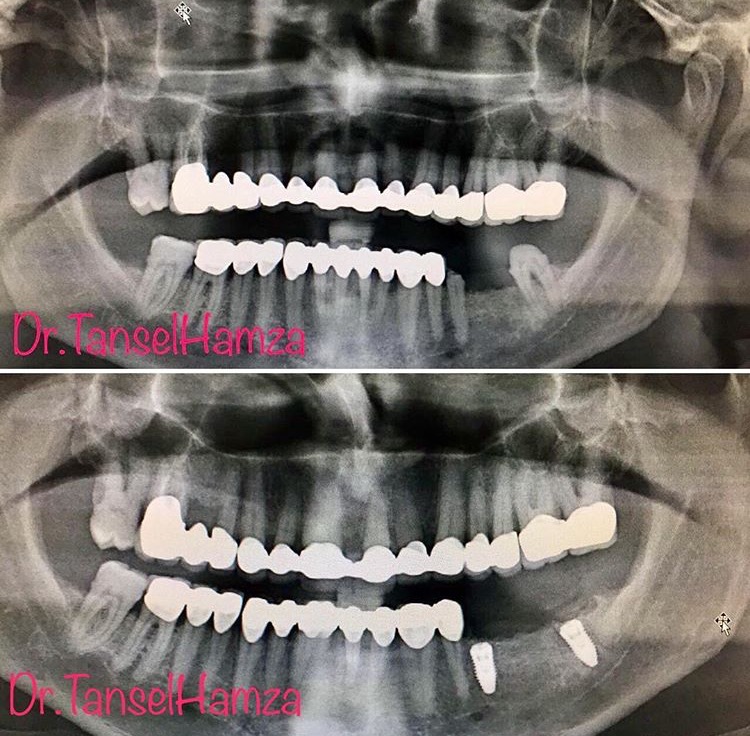

Diş Estetiği ve İmplant (Bölüm 2)

Tansel Hamza